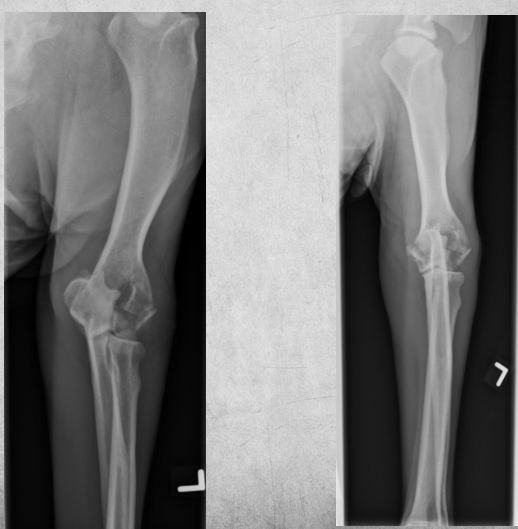

11

4 years old male castrated Labrador cross

Sudden and acute lamness while playing with ball

A

Osteolysis of the proximal third of the tibial diaphysis and very mild irregular periosteal reaction.

There is a short oblique fracture through the tibial diaphysis with several small associated fragments, mild medial and proximal displacement of the distal segment. A transverse fracture of the fibula is present at the same level.

Diagnosis: Osteosarcoma with pathologic fracture.